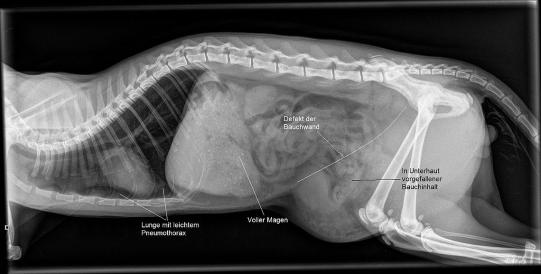

Ein Röntgenbild bestätigt den Verdacht, dass die Katze eine Bauchwandhernie aufweist. Hierbei reisst die Bauchdecke an einer oder mehreren Stellen, und Bauchinhalt wie Därme, Milz und Blase rutschen aus der Bauchhöhle in den Unterhautbereich.

Ausserdem weist Fred einen geringen Pneumothorax auf - aufgrund des Aufpralles hat die Lunge einen Riss erlitten, und Luft ist in den Zwischenraum zwischen Lunge und Brustkorb getreten.